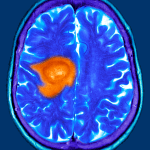

In August 2024 researchers at the University of California, Los Angeles (UCLA) announced the launch of a “first-of-its-kind” clinical trial to evaluate the safety and effectiveness of a cancer vaccine that targets H3 G34-mutant diffuse hemispheric glioma, a “highly aggressive” brain tumour that is “typically” found in adolescents and young adults. The vaccine, developed at UCLA, is designed to target genetic mutations of the H3-3A gene. The trial will start with patients over the age of 18 before expanding to include patients as young as 5 years who have a confirmed diagnosis of H3 G34-mutant diffuse hemispheric glioma.

One of the “most lethal forms of paediatric brain cancer”, H3 G34-mutant diffuse hemispheric glioma is a “highly aggressive brain tumour” primarily characterised by a mutation in the H3-3A gene. This gene encodes an “important regulatory component” on histone H3. The mutation causes “significant disruptions” in RNA processing, which has “wide-ranging influences on cancer behaviour and response to treatment”. UCLA Health is the only centre in the US that is investigating immunotherapy for this type of glioma.